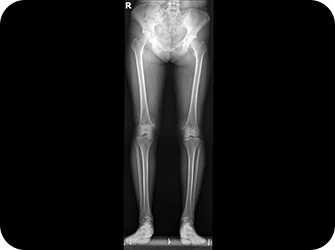

발의 아치가 무너지거나 발목 관절이 틀어지면 연쇄적으로 척추, 골반 불균형과 다리 길이 차이를 유발할 수 있습니다. 연산당당 족부 교정 장치는 이러한 전신의 구조 문제를 개선하기 위해 발의 아치와 발목 관절을 제자리로 교정합니다.

발과 걸음걸이 교정

올바른 체형 개선

척추/관절 손상 방지

통증 완화

다리길이 측정

엑스레이 검사